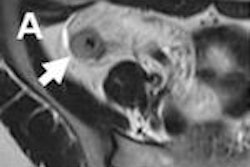

In a 41-year-old female patient with MS, misaligned cervical vertebrae (C1, C2, and C3) were causing blocked cerebrospinal fluid flow, and malrotations of these vertebrae were initially discovered and visualized on the Upright MRI scanner, according to the vendor. The study showed that the vertebrae were rotated 5° to 6° from their normal alignment.